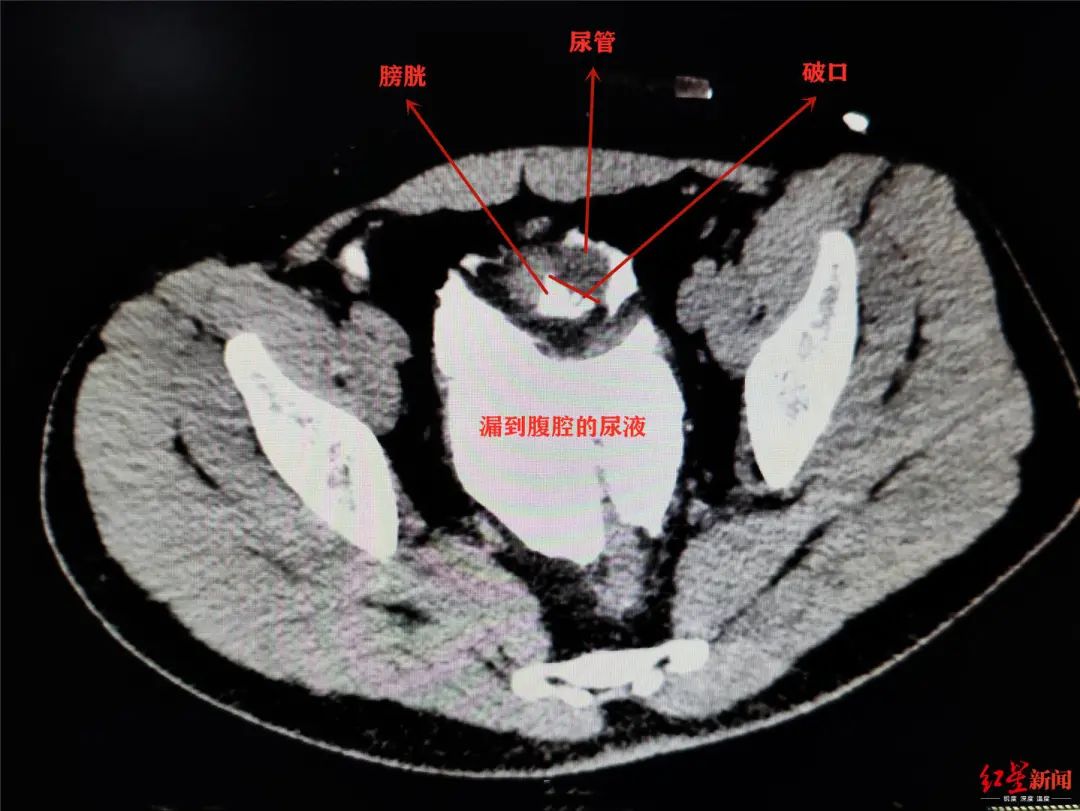

酒后憋尿摔一跤 小伙子膀胱磕破了!医生紧急修补

酒后憋尿摔一跤,成都小伙子膀胱磕破了.